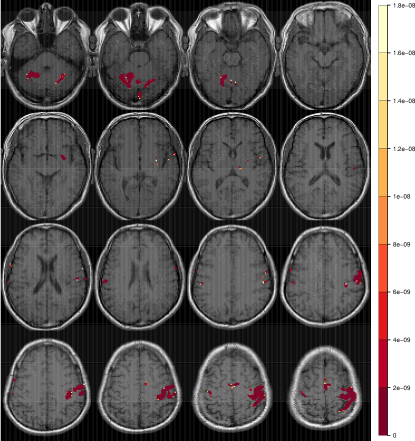

Refer to caption

Figure 5: Composite activation map for slices 7 through 22, of the right-hand finger-thumb opposition task experiment obtained using (a) all twelve fMRI studies and (b) all but the tenth and eleventh studies. Displays are as in Figure 2.

The coefficient of variation in the jackknife-estimated standard deviations of ζ^jfragments^𝜁fragmentsj\hat{\zeta}_{-j}s was around 0.0501: this indicates that the arc-sine transformation was able to stabilize the variance substantially. Figure 4 plots the computed τjfragmentsτfragmentsj\tau_{-j} against j𝑗j for each j=1,2,,12fragmentsj1,2,,12j=1,2,\ldots,12. Note that the values of τ10fragmentsτfragments10\tau_{-10} and τ11fragmentsτfragments11\tau_{-11} are fairly high: indeed, the corresponding fMRI maps would be identified as significant outliers if we used an expected FDR (eFDR) of q=0.05fragmentsq0.05q=0.05, but not so using an eFDR of q=0.01fragmentsq0.01q=0.01. Thus they may be considered to be moderate outliers: this finding is in keeping with the general impression we obtained from Figure 2a. Eliminating the moderate outliers increases the summarized overlap measure: smω(10,11)=0.287fragments𝑠𝑚ωfragments(10,11)0.287{}^{s}_{m}\omega_{-(10,11)}=0.287 (sω(10,11)=0.432fragments𝑠ωfragments(10,11)0.432{}^{s}\omega_{-(10,11)}=0.432). Figure 5a and b displays the composite activation map obtained upon combining all the replications and all but the tenth and eleventh replications, respectively. Each composite map was obtained by averaging the t𝑡t-statistics for each study [47] and determining activation as before using the Random Field theory of [45] at 5% significance. The activated regions in Figure 5b are slightly more defined than in Figure 5a. This makes sense because the effects of the less reliable studies have been removed in constructing the composite activation map of Figure 5b.